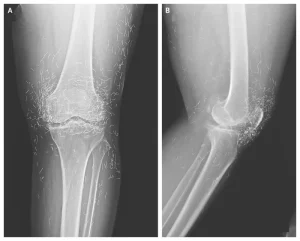

A routine X-ray revealed a startling surprise when doctors examined the knees of a 65-year-old woman suffering from severe joint pain. What appeared at first glance to be a standard imaging scan of osteoarthritis turned out to be far from ordinary. The X-ray showed hundreds of tiny gold needles embedded deep in her knee tissue, a discovery that left medical professionals both intrigued and concerned. The woman, whose identity was kept private, had sought relief from chronic pain that had progressively worsened over the years, leading to stiffness and limited mobility. When traditional medical interventions failed to alleviate her discomfort, the decision to pursue alternative therapies ultimately revealed an unexpected risk of unconventional treatments. This case underscores the sometimes-unseen consequences of popular complementary medicine practices and offers a cautionary tale about the balance between seeking relief and exposing oneself to potential harm.

The woman’s case was recently documented in the New England Journal of Medicine, drawing international attention from both medical professionals and the general public. Her X-rays, showing hundreds of tiny gold needles deeply embedded in her knee tissue, serve as a powerful visual reminder of the potential consequences of extreme alternative therapies. While the procedure may have been intended to help alleviate her suffering, it also exposed her to risks that could complicate future treatments and imaging studies. Experts stress that patients considering acupuncture should be fully informed about the type, frequency, and potential side effects of any treatment, especially when permanent implants are involved. In the end, her experience underscores a broader lesson: the pursuit of pain relief must be balanced with a careful understanding of medical risks, informed decision-making, and consultation with qualified healthcare providers. Cases like hers remind both practitioners and patients that even seemingly harmless alternative therapies can carry serious, sometimes life-altering consequences when used outside standard guidelines.